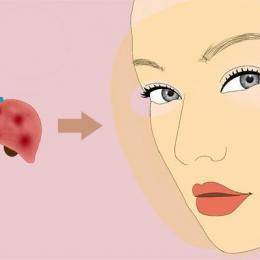

乙肝是我们现行比较流行的一种疾病,此病不仅发病人数非常多,而且还会传染给身边朋友及家人,因此对于乙肝我们一定要详细了解,[详细]